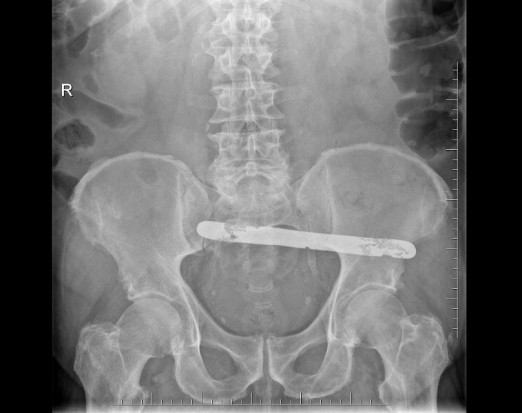

В больнице Подкарпатского воеводства Польши врачи забыли в брюшной полости у мужчины металлический предмет и зашили разрез. Он ходил с дополнительным грузом в теле полтора года.

Благодаря Уполномоченному по правам пациентов мужчина получил компенсацию за оставление в его теле инородного тела во время операции по удалению желчного пузыря.

О том, что у него в брюшной полости забыли инструмент пациент узнал только через полтора года, когда попал в ту же больницу. Медики отказались признавать ответственность за ошибку и предположили, что посторонний предмет остался в теле мужчины во время другой операции.

Суд не согласился с позицией больницы и сослался на заключение эксперта, которое четко показало, что до операции была проведена диагностика брюшной полости и инородных тел тогда не нашли.

В силу всех обстоятельств суд присудил пострадавшему пациенту компенсацию в размере 40 тысяч злотых, которую апелляционный суд увеличил до 65 тысяч злотых (14,6 тысяч долларов).